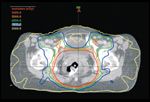

FIGURE 2

Conventional Radiotherapy Plan FIGURE 3

IMRT Treatment Plan

Figures 2 through 5 compare a 3D conformal radiation therapy plan (Figures 2 and 4) with an IMRT-based treatment plan (Figures 3 and 5). Figures 6 and 7 illustrate a representative IMRT field with associated dose fluence map. The differences in sagittal radiation dose distribution are shown between a 3D conformal plan (Figure 8) vs IMRT plan (Figure 9). A clinically significant advantage of IMRT includes a reduction in normal (high-dose) tissue irradiation resulting in less acute and chronic radiation-related toxicities, including nontarget bowel, bladder, and genitalia. These can often be significant using conventional radiation techniques, leading to potential treatment breaks with poor outcomes. Additionally, IMRT may permit safe radiation dose escalation in selected clinical situations.